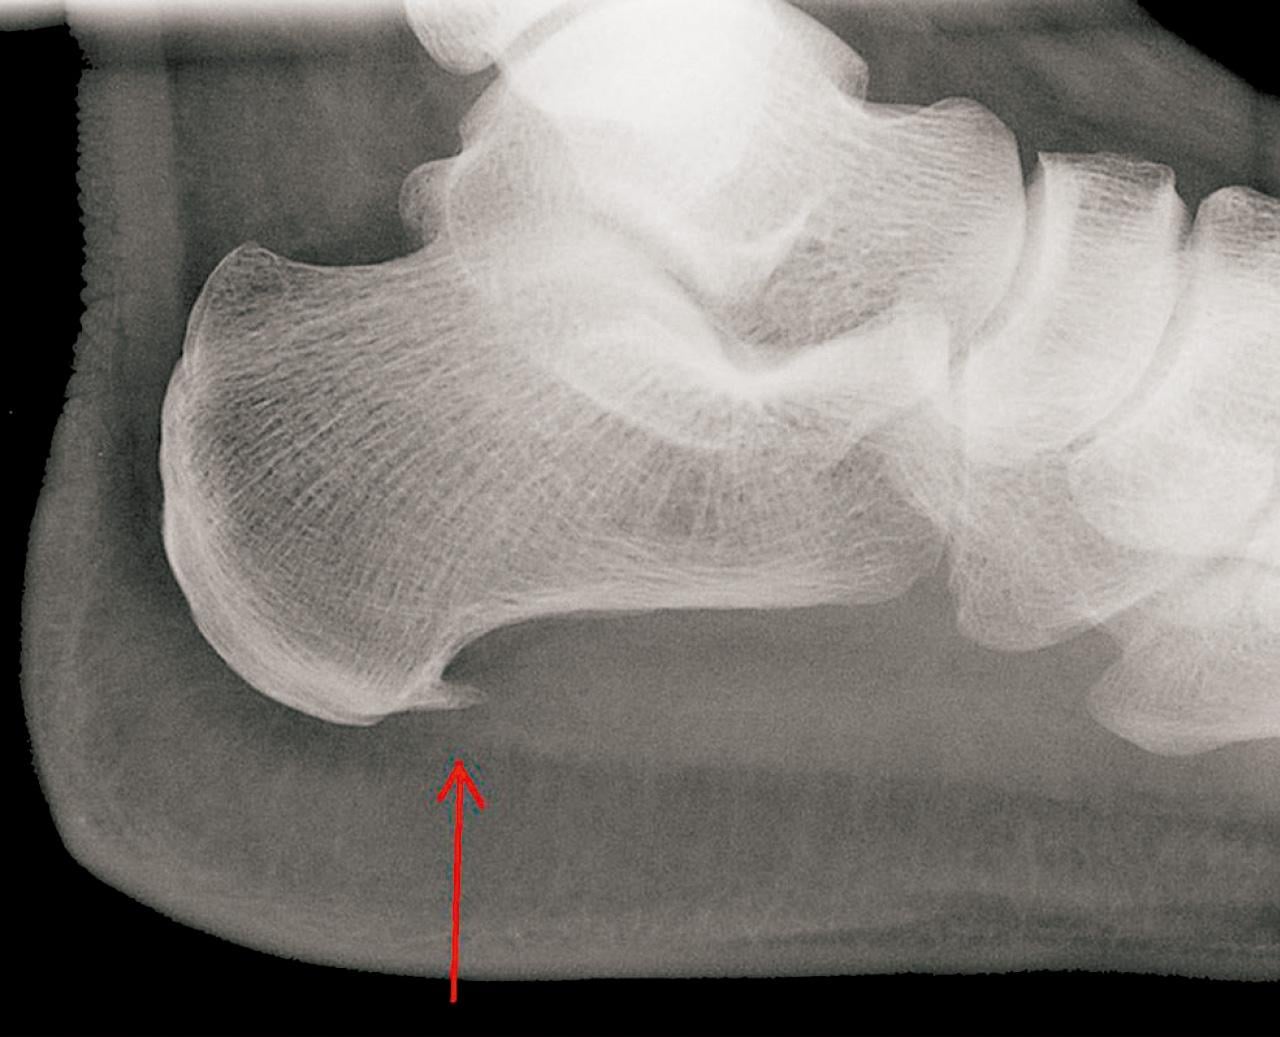

骨刺害人?

骨刺,醫學上稱為「骨質增生」,是骨骼因長期磨損或壓力而在關節邊緣產生的增生現象,常見於頸椎、腰椎、膝蓋等,通常被視為老化所致。但骨刺並非老年人的專利,長期姿勢不良、過度使用關節或運動傷害等,都會加速形成骨刺。

骨刺的主要成因是關節軟骨退化。當軟骨因磨損變薄,骨骼間摩擦增加,身體為減少摩擦會在關節邊緣增生骨質,形成骨刺。這些骨質本身不會直接引起疼痛,但若壓迫到神經、肌肉或韌帶,可能導致疼痛、麻痺或活動受限等。